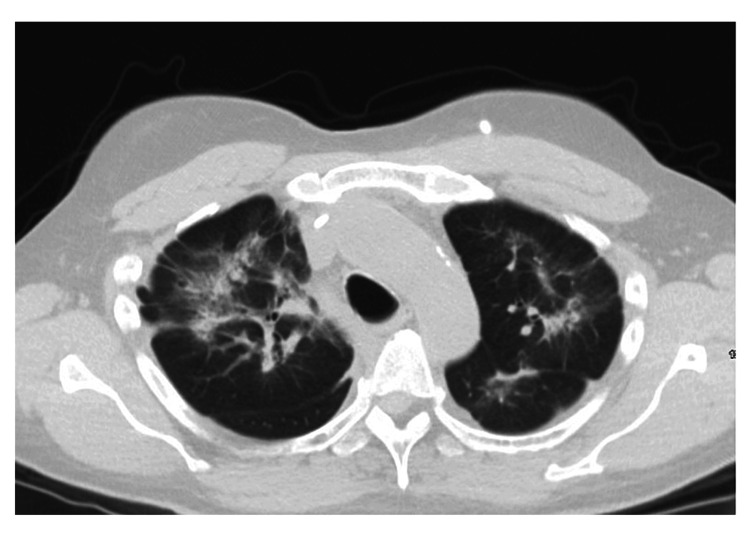

After the evaluation of the patient in the clinic, the patient was sent for a repeat CT scan which showed diffuse interstitial opacities without honeycombing as seen in Figure 1.